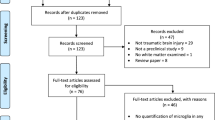

Microglial process convergence increases following axonal injury

To investigate the potential for microglial process convergence occurring on injured axonal swellings or intact myelinated fibers in the human brain, multiplexed immunohistochemistry against the anterogradely transported protein, amyloid precursor protein (APP) to visualize injured axons, myelin basic protein (MBP) to visualize intact myelinated axons, and ionized calcium-binding adaptor molecule 1 (Iba-1) to visualize microglia processes was done on human postmortem tissue from the DoD/USU tissue repository. When all fibers that were analyzed across all cases were collated as APP + injured axonal swelling or MBP + intact myelinated fibers, it was found that more Iba-1 + microglial processes/um of the perimeter were in direct contact with APP + axonal swellings compared to MBP + intact myelinated fibers (Fig. 1A; U = 32,240, p = 2.4 × 10–4). The paraffin sections were thin sections, precluding the ability to perform 3D reconstructions of the axonal swellings, as we had done for our previous studies26,27. As a single 2D image of the axonal segments is likely to be missing processes that are out of the plane of section, we also investigated the number of Iba-1 + microglial processes that were within 5um of the axonal segments. More microglial processes were found within 5um of APP + axonal swellings compared to MBP + intact myelinated fibers (Fig. 1B; U = 34,260, p = 2.99 × 10–6), indicating that more microglial processes are close to the injured axonal swellings.

After completing this initial analysis of the overall comparison between APP + swellings and MBP + myelinated fibers, the cases were un-blinded. Following case unblinding, it was discovered that some APP + axonal swellings were identified in control individuals and some MBP + myelinated fibers were analyzed from individuals that had DAI (Fig. 2). Therefore, the analyzed fibers were organized into four groups: (1) MBP + intact myelinated fibers in control tissue, (2) MBP + intact myelinated fibers in DAI tissue, (3) APP + axonal swellings in control tissue, and (4) APP + axonal swellings in DAI tissue. When the data was stratified by axonal injury and DAI cases we found more microglial process convergence occurring directly onto APP + injured axonal swellings, specifically within tissue with verified DAI (χ2(3) = 15.53, p = 0.001; Fig. 3A). There were also significantly more microglia processes within 5 μm of APP + injured swellings in both control and DAI tissue as compared to MBP + fibers in control postmortem samples (χ2(3) = 21.97, p = 6.61 × 10–5; Fig. 3B).